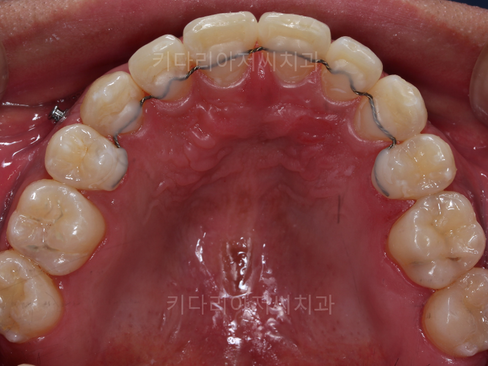

연산동사랑니치과 키다리아저씨치과에 처음 내원하셨을 때의 파노라마 및 씹는 면 구내사진입니다.

교정 종료 후 오른쪽 아래 사랑니 발치 전후 사진입니다.